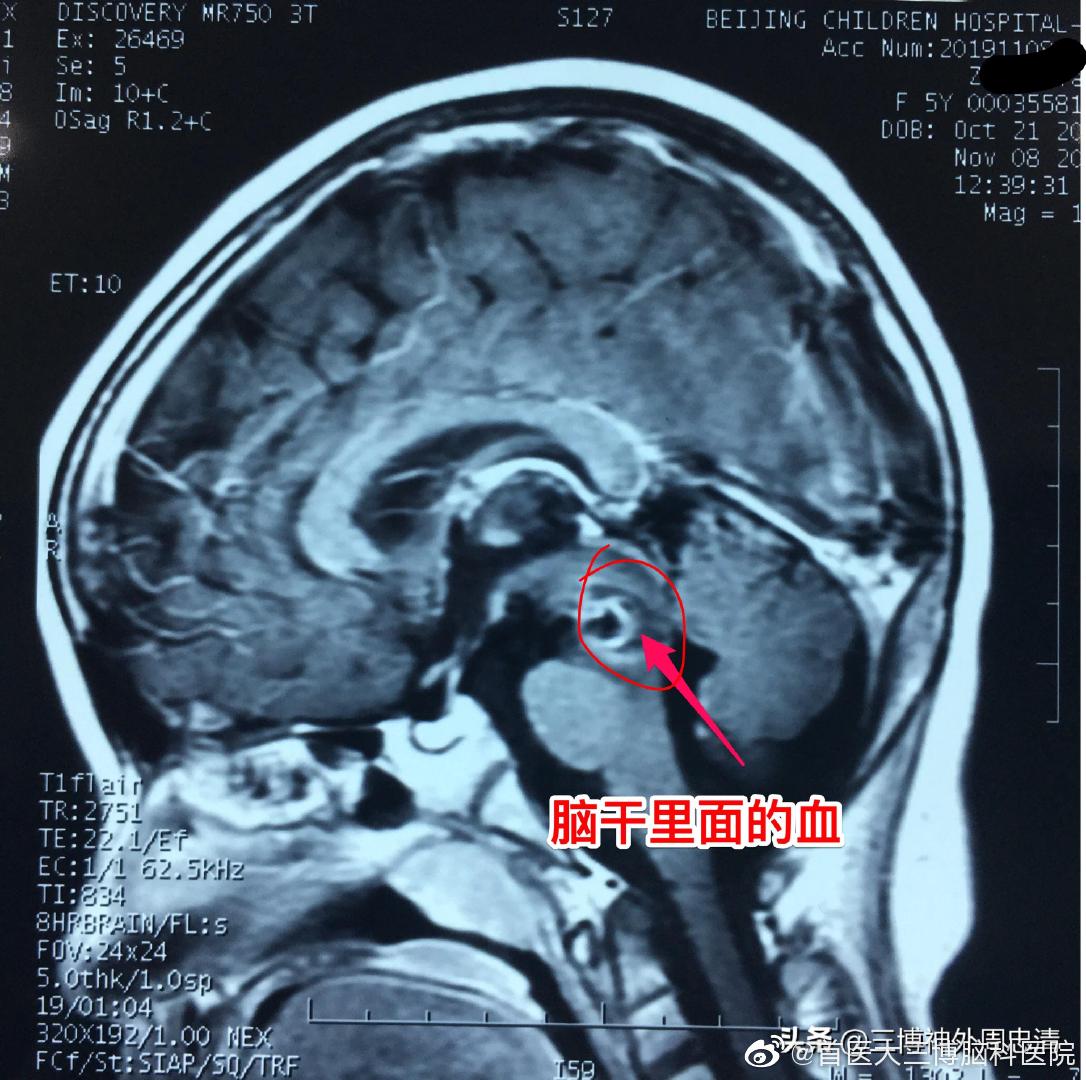

脑干血栓

五岁女孩子突发脑干出血!危在旦夕